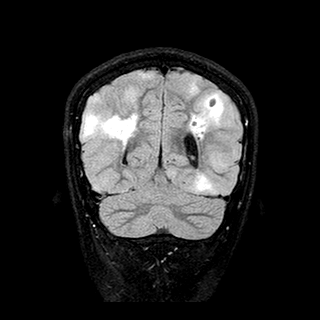

F. � un ragazzo di 12 anni che dall'et� di 5 mesi ha presentato: rabdomiomi cardiaci (evidenziati gi� alla nascita per la presenza di un soffio), 2 formazioni iperecogene in prossimit� del ventricolo laterale sinistro (eco cerebrale), focolai di edema cortico-sottocorticale bilateralmente in sede parietale postero-superiore e multipli noduli subependimali ventricolari con calcificazioni (RMN cerebrale), crisi epilettiche parziali (clonie mano destra e bocca), chiazze ipocromiche al tronco ed arti (pi� di 10). Le crisi, caratterizzate da blocco dello sguardo, scialorrea e disorientamento, sono diventate sempre pi� frequenti, associate a episodi di riso prolungato e ritardo psico-motorio. Viene da subito iniziata terapia antiepilettica con vigabatrin, acido valproico e levetiracetam. A 10 anni comparsa di angiofibromi facciali. Eseguita analisi molecolare che ha evidenziato mutazioni de novo in TSC2. Alla RMN di controllo eseguita a 12 anni: �in entrambe gli emisferi, numerosi tuberi cortico-sottocorticali con aspetti calcifici; 3 noduli subependimali in prossimit� del forame di Monro.� FO: �Amartomi retinici OS�. Il quadro clinico e l'indagine genetica hanno permesso di formalizzare la diagnosi di sclerosi tuberosa (Figura 1 e Figura 2).

Figura 2.